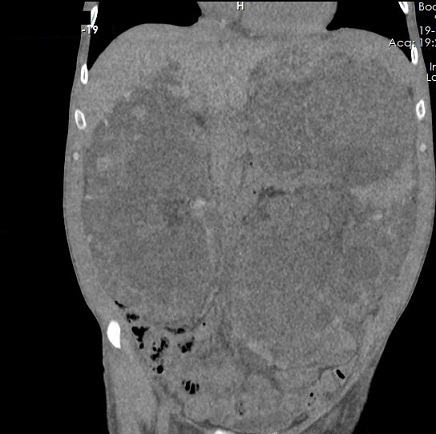

A 49-year-old male patient was diagnosed with ADPKD while the evaluation of urinary tract infection in 2010. Renal failure progressed quickly in the patient after the diagnosis of polycystic kidney disease. Renal replacement therapy was begun due to end-stage renal failure in June 2013. His father was also a dialysis patient secondary to ADPKD. The patient was too slim with 56 kg weight and 18.9 BMI. Physical examination revealed that the abdomen was distended because of the polycystic kidneys. He said that he suffered from nutritional problems due to gastro-intestinal disturbances and vomiting secondary to the pressure of the kidneys. Computed tomography revealed giant polycystic kidneys covering most of the abdominal space (Figure 1a, 1b).

Figure 1b. Coronal view of the abdominal tomography. Huge polycystic kidneys are visible and the intestinal

structures are deplaced to the caudally. There are also multiple cysts in the liver